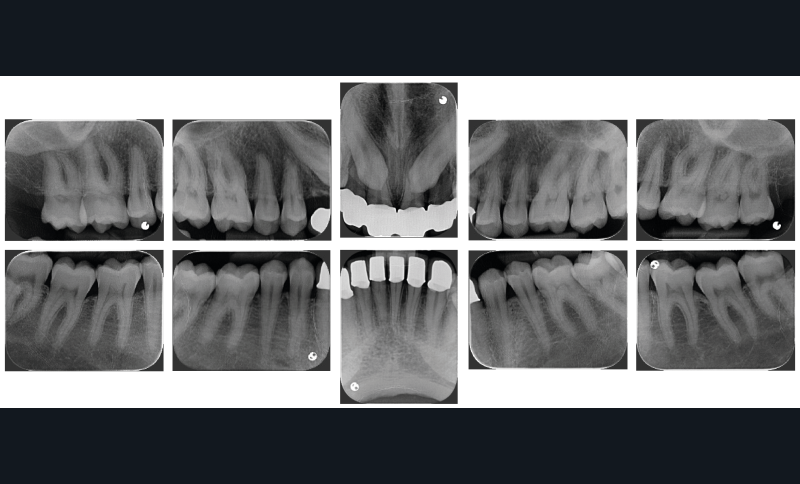

À l’examen endobuccal de première consultation (fig. 1), nous notons la présence d’un bridge maxillaire céramo-céramique sur infrastructure en zircone avec 12, 11, 21 et 22 couronnes moyens d’ancrage et 13 et 23 intermédiaires de bridge en extension. Les incisives et canines mandibulaires ont également été couronnées individuellement. Le patient nous informe que ces soins ont été réalisés pour répondre à sa demande esthétique. L’examen radiologique (fig. 2) révèle la présence de deux canines maxillaires incluses et nous montre qu’aucune dent n’a subi de traitement endodontique.